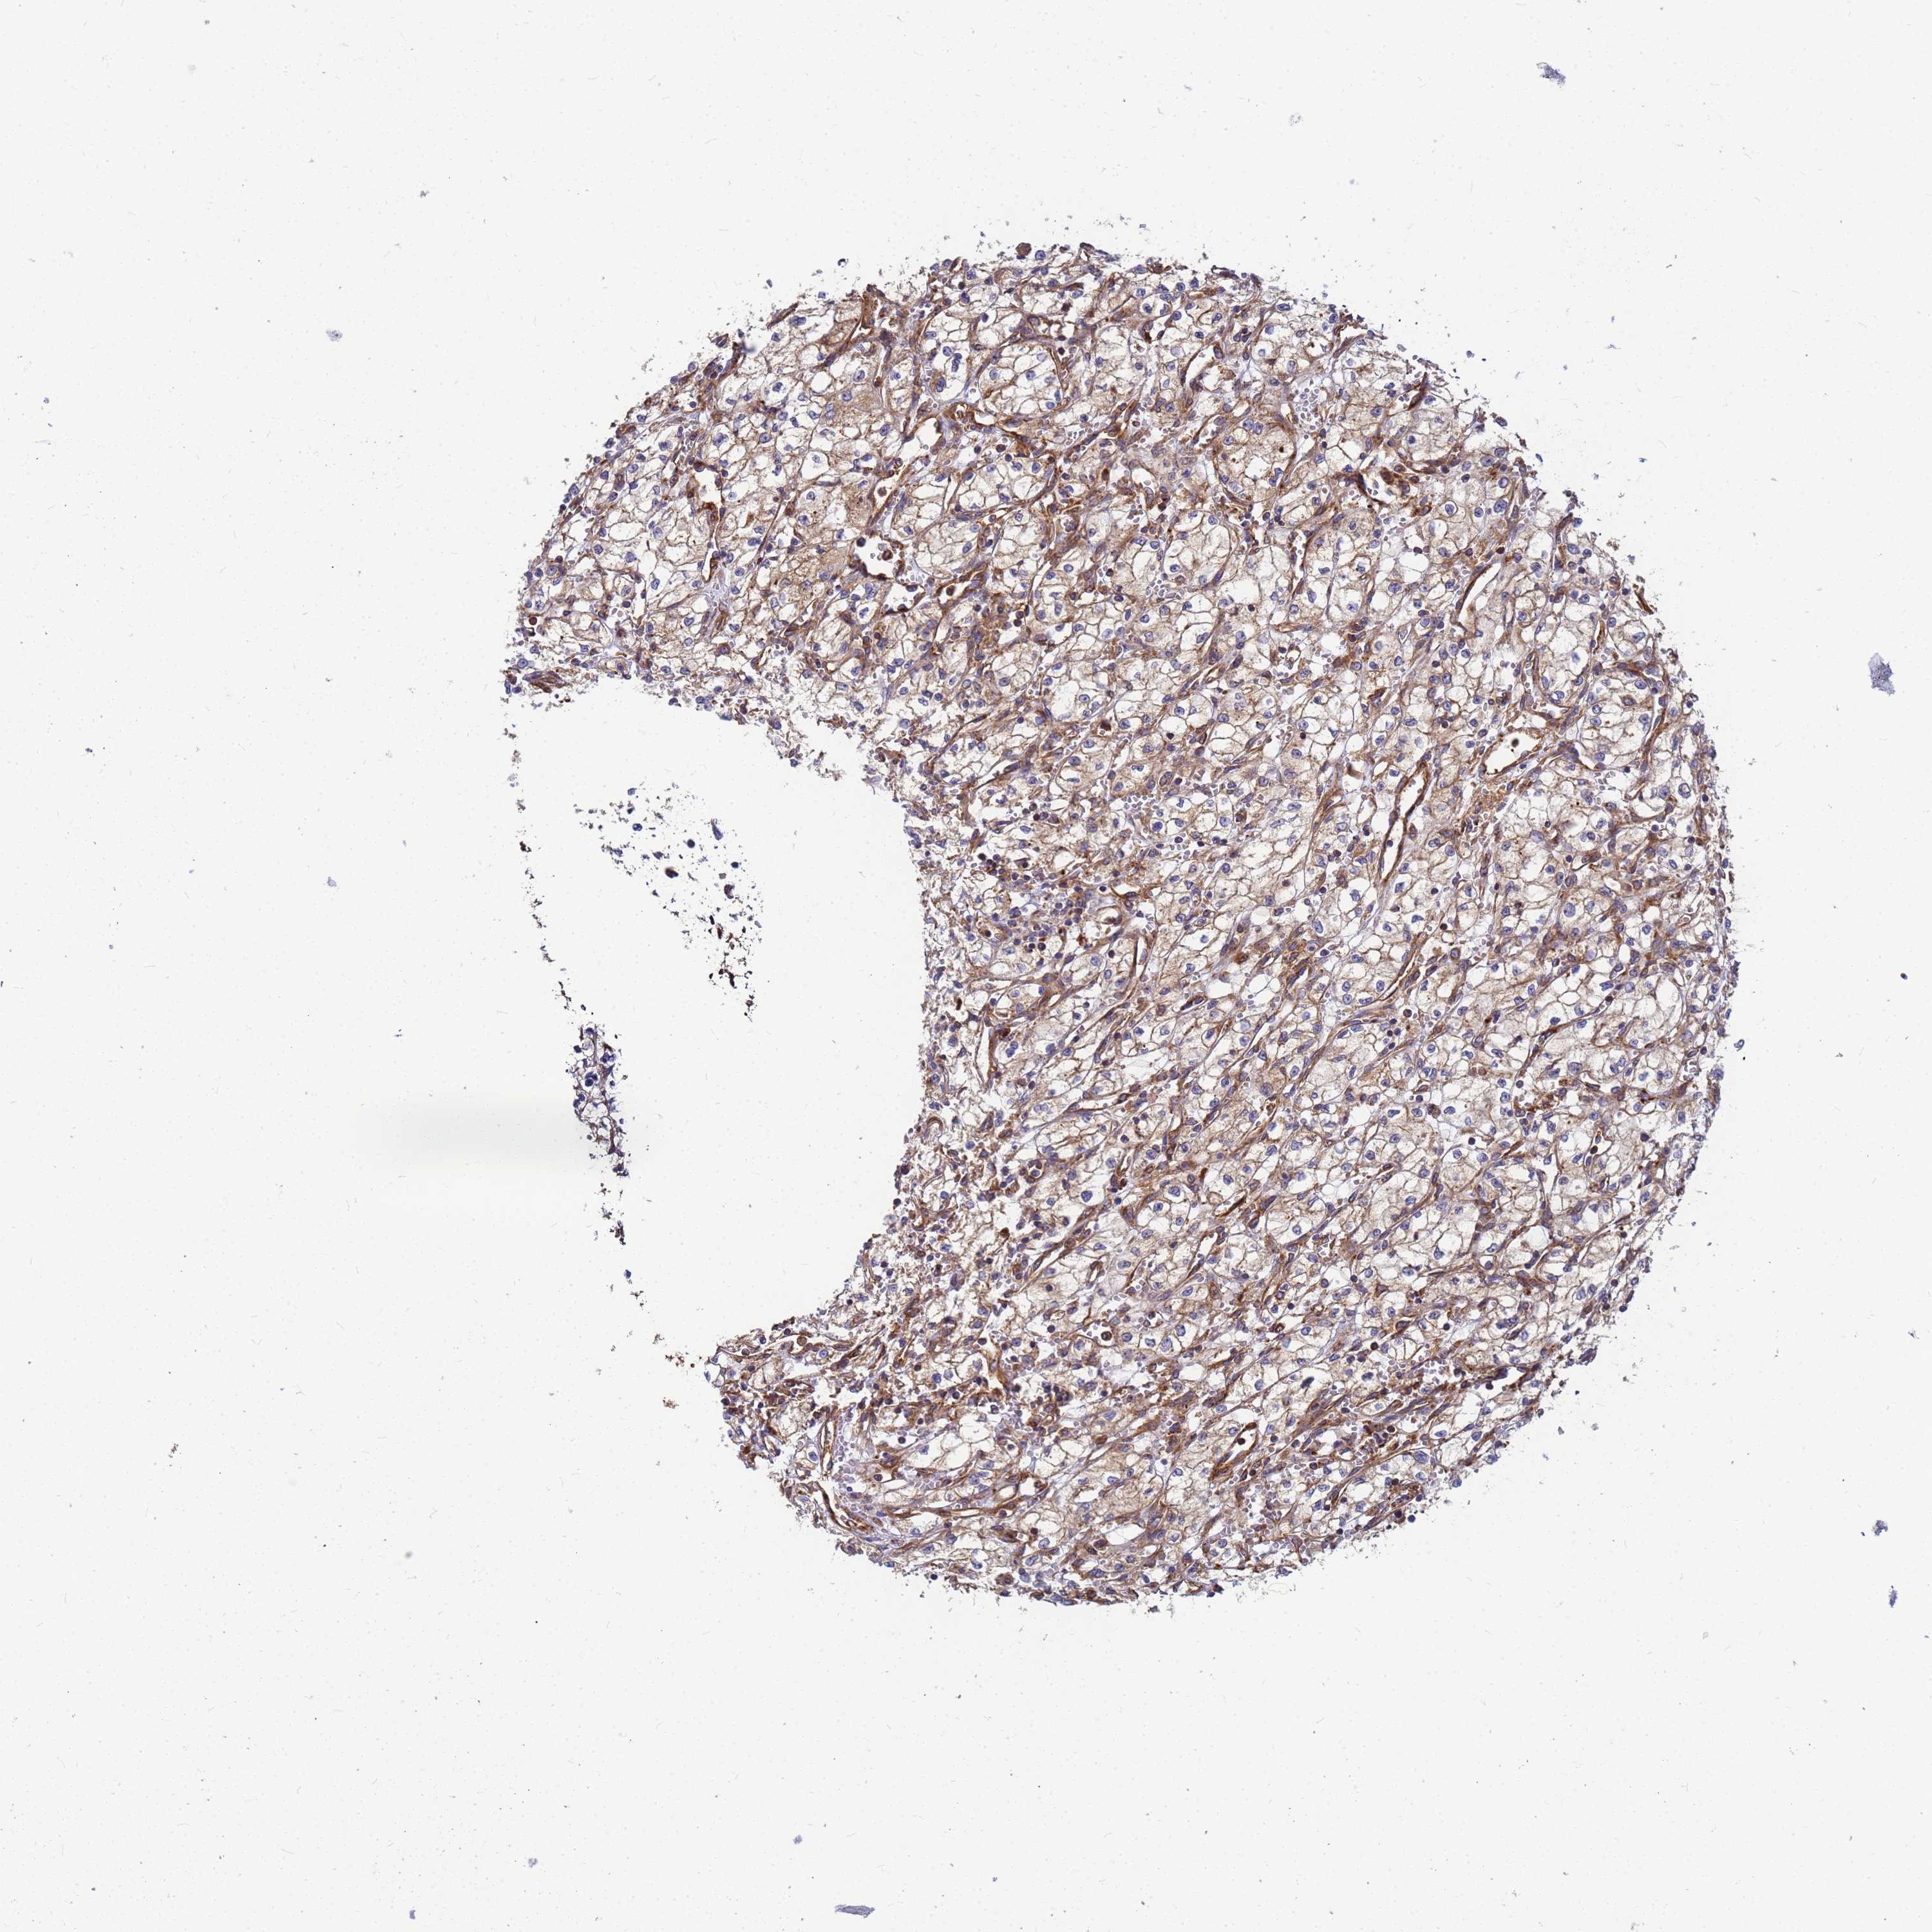

KIDNEY RENAL CLEAR CELL CARCINOMA (TCGA) - Interactive survival scatter ploti

& Survival analysisi

Kaplan-Meier plots summarize results from analysis of correlation between mRNA expression level and patient survival. Patients were divided based on level of expression into one of the two groups "low" (under cut off) or "high" (over cut off). X-axis shows time for survival (years) and y-axis shows the probability of survival, where 1.0 corresponds to 100 percent.

C2CD5 is not prognostic in Kidney Renal Clear Cell Carcinoma (TCGA)

: 14.46

Average pTPM 16.1

Number of samples 521